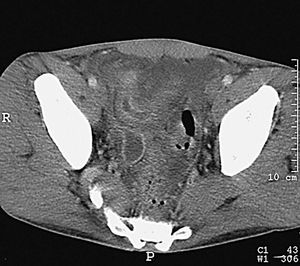

Desde el punto de vista tomodensitométrico (fig. 12) y de la RM los criterios semiológicos son más o menos similares: el engrosamiento mural y la hiperemia característica de una situación inflamatoria activa. Se describe el hecho de que el engrosamiento mural del colon suele ser más marcado en la colitis granulomatosa que en la ulcerosa, lo mismo que la irregularidad de los contornos, que suele ser también más acentuada en los casos de colitis granulomatosa.

Fig. 12.--Enfermedad de Crohn. A) La tomografía computarizada (TC) muestra la afectación del colon de carácter segmentario.(B) En la reconstrucción en plano coronal (MPR) puede apreciarse el marcado engrosamiento mural del colon descendente.